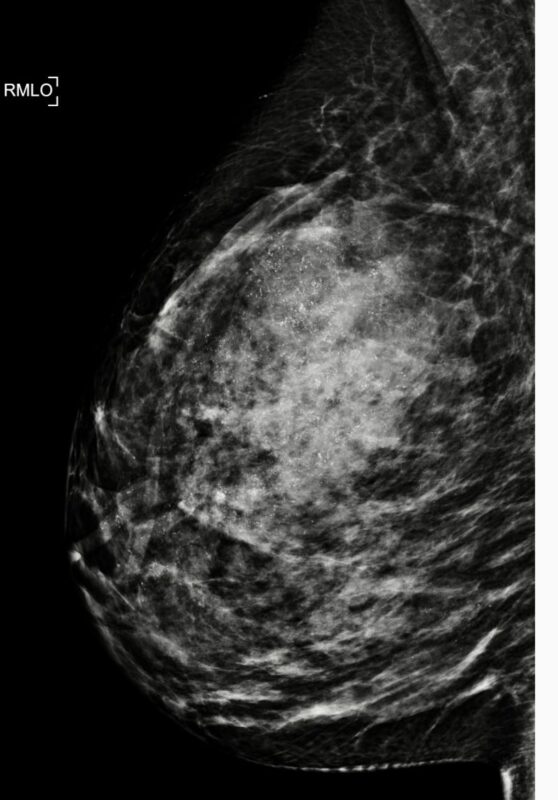

A new study published examines a provocative question: could radiotherapy (RT) alone be a safe and effective alternative to surgery in selected cases of ductal carcinoma in situ (DCIS)?

Title: Radiotherapy as a surgical alternative in ductal carcinoma in situ (DCIS): long-term survival benefits and predictors of invasive progression risk